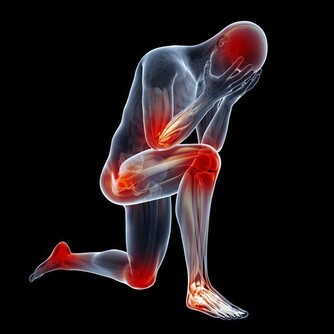

先說“痛”字,主要是發病時患者的關節會產生劇痛,就像身體的某個部位長出刺來一樣,想想就內心就覺得疼啊!再說“風”,這說明痛風也就是痛一會兒,時間不是很長,就像一陣風刮過之後,就沒了!

據流行病學的相關數據統計顯示,大約10%的高尿酸患者會發生痛風,痛風患者40%可繼發腎臟損害的表現!而且實際情況當中可比這個40%要高很多。

什麼意思呢?意思是雖然痛風一次次的發生,但是每次發生痛風都會對腎臟造成一定的損害!